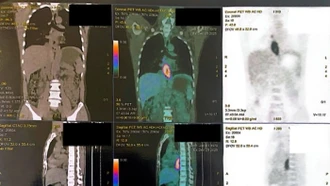

Người đàn ông nhập viện vì nuốt nghẹn, sụt 5 kg trong một tháng, đi khám phát hiện cùng lúc hai ung thư biểu mô vảy ở thực quản và hầu miệng.